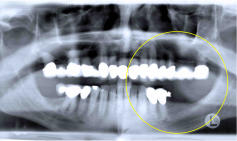

Situation vorher (Brückenanhänger,

abnehmbar mit Geschiebe, ist bereits

entfernt)